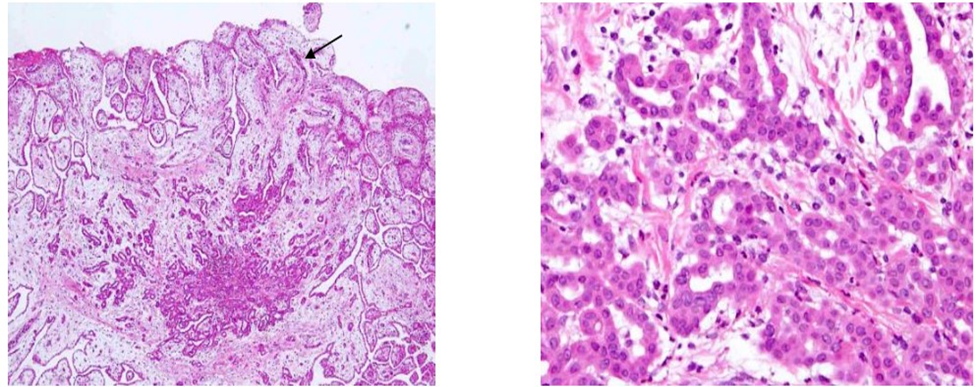

Microscopic examination showed that a papillary pattern accompanied by a glandular pattern, and the papillary areas were lined by a single cuboidal mesothelial cells (Figure 3), with one case (Figure 4, Case 8), having a mild nuclear atypia. In general, the mesothelial cells lacked mitotic activity. In addition, less than 1% of cells were positive for MIB-1 antibody (Figure 5). Immunohistologic studies showed a positive calretinine, CK7 (Figure 6) and D2-40 (Figure 7) and a negative CEA. In case 8, submesothelial invasive tumor of higher cytologic grade was detected in one of 23 sections from resected specimen.

Figure 8: Invasion foci found in Case 6. Atypical cells mimicking MPM invade into the submesothelial tissue (case 8).

Patients (case 1, 2, 5, and 7) treated by LHIPEC alone were alive with WDPM (case 2, 5, and 7) from 11 to 77 months or without WDPM (Case 1) after 92 months (Table 2). PCI of case 1 at the 1st LHIPEC was 3, but it was 0 at the second laparoscopy, performed 6 months after the 1st LHIPEC. PCI of case 2 at the 1st LHIPEC was 30 (Figure 9), and WDPM was completely disappeared at the 2nd laparoscopy (Figure 10). However, PCI of case 7 was not changed at the 1st LHIPEC (PCI of 36) and 2nd LHIPEC (PCI of 36). PCIs of Case 3 and 4 at the 1st LHIPEC were 15, and 16, and those at the laparotomy became 3 and 13. Accordingly, complete resection could be done in the two cases, and they are alive without recurrence. In contrast, PCIs of case 8 and 9 at the laparotomy were 26 and 23, and those could not be reduced by LHIPEC and IP chemotherapy to the levels to perform complete resection. Additionally, small bowel mesentery in these 2 cases was diffusely involved, Case 8 died of mesothelioma recurrence in pleural cavity and abdominal wall, and the histology showed MPM (Figure 11). Case 9 is alive with mesothelioma recurrence in peritoneal cavity and the pathologic diagnosis was biphasic type of DMPM. Case 5 committed suicide.

Figure 11: Histological finding of abdominal wall recurrence (Case 8) shows typical epithelioid type of malignant peritoneal mesothelioma.

PCI of patients who received CC-0 resection after LHIPEC plus IP chemotherapy change from 15 to 3 (case 3) and 16 to 13 (case 4). Additionally, cycles of IP chemotherapy in case 3, and 4 were 7 and 5 cycles. However, lesion size scores on small bowel mesentery could not reduced in case 8 and 9, resulting in performing incomplete cytoreduction. IP chemotherapy cycles of these patients were 3, and 0 cycles. From these results suggest that more than 5 cycles of IP chemotherapy are needed to reduce PCI levels and small bowel PCI levels to perform CC-0 resection. Deraco M et al. reported 45 WDPM patients were treated with cytoreductive surgery using peritonectomy technique plus intraoperative HIPEC. There were 4 deaths and 5 years overall survival was 80%, and 8 patients had disease recurrence. On univariate analysis preoperative CT, high PCI and severe morbidity associated with reduced survival. On multivariate analysis only preoperative CT (hazard ratio 32.6) and High PCI (HR=21.7) remained significant risk factors. As prognostic factor, Churg A proposed a invasive foci in the WDPM 13). Invasive foci include small bland-appearing mesothelial glands in a fibrotic stroma, solid or near solid areas of bland mesothelial cells, cytologically higher grade lesions appearing as sheets of atypical mesothelial cells or atypical cells forming glands, or invasion into the subperitoneal tissues. They alert that WDPM having these foci tend to have possibility of recurrence [13]. In the present study, case 8 shows submesothelial invasive foci of higher cytologic grade was detected in one of 23 sections from resected specimen. This case developed recurrence in abdominal wall 97 months after treatment, and the histology showed epitheliod type of MPM.